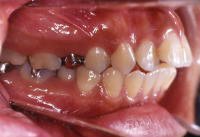

矯正(上あご前突)

術前

術後

矯正(下あご前突)